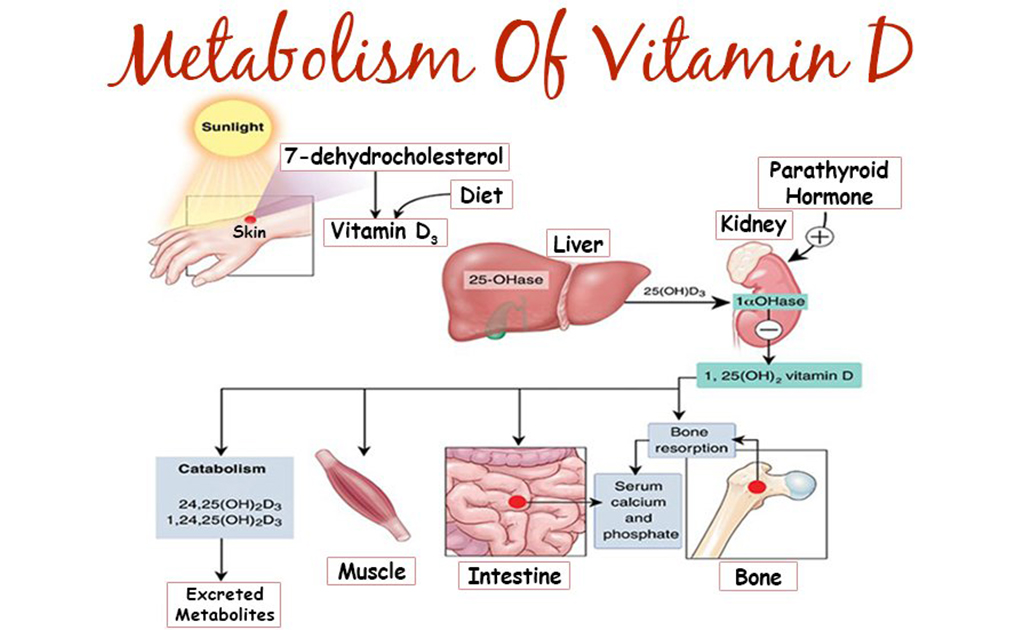

শরীরে ভিটামিন ডি-এর ঘাটতি থাকলে কী করে বুঝবেন?

0 SHARES Share Tweet ‘ভিটামিন ডি’ করোনাকালে বেশ পরিচিত হয়ে উঠেছে লোকমুখে, বিশেষত এর রোগ প্রতিরোধ ক্ষমতা বৃদ্ধিকারী গুণটি...